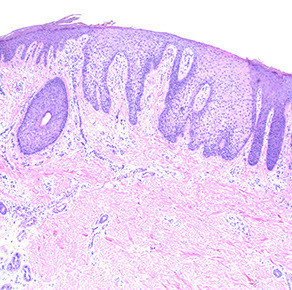

Syringocystadenoma Papilliferum (SCAP)

aka papillary syringadenoma

b9 sweat gland proliferation that arises in the middle of a nevus sebaceus

- warty tumor of scalp, neck, and face that can occur at any age

- clinically is a slow growing or recent change in a brithmark, may be crusty and start to bleed

- 1/3 have adjacent nevus sebaceus, 10% with adjacent BCC

- malignant counterpart is syringocystadenocarcinoma papilliferum

Micro: glandular papillary prolif connected to skin surface

- has ducts that look similar to sweat ducts sometimes, which are lined by cuboidal cells, that eventually empty to skin surface

- dense plasma cell infiltrate in the dermis, or in the middle of the papillary structures

Nevus sebaceus of Jadassohn

SCAP (darker blue at bottom middle) growing in background of nevus sebaceus